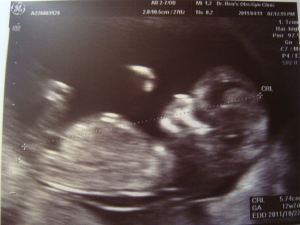

(孫寶寶 12禮拜)

當電腦那端出現這個畫面時,

我足足尖叫了一分鐘!! 又叫又跳又拍手!!

他這才把另一張超音波相片拿到鏡頭前給我們看。 原來之前的“溫度計”是驗孕棒, 證實女兒"有了"! 他們一直等到看了婦產科醫生,都三個月穩定了,才讓雙方家長知道這個喜訊。